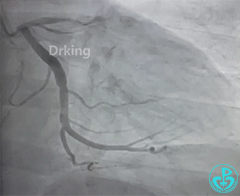

左冠造影:

导丝怎么扩收藏:器械难以通过的CTO病变之技术图谱_https://www.jmylbn.com_新闻资讯_第2张

导丝怎么扩收藏:器械难以通过的CTO病变之技术图谱_https://www.jmylbn.com_新闻资讯_第3张

导丝怎么扩收藏:器械难以通过的CTO病变之技术图谱_https://www.jmylbn.com_新闻资讯_第4张

导丝怎么扩收藏:器械难以通过的CTO病变之技术图谱_https://www.jmylbn.com_新闻资讯_第5张